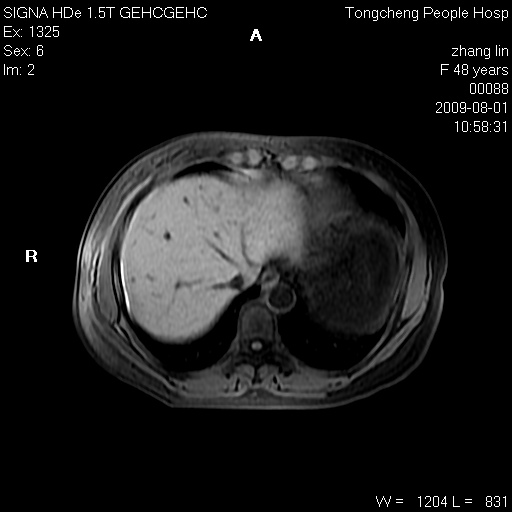

女,48岁。健康体检,彩超发现右肾占位性病变。平素健康。

临床诊断:右肾占位性病变,性质待定(囊肿?肿瘤?)。

上中腹部mr平扫+增强扫描,图像如下:

右肾上极见一类圆形病灶,t1wi呈等信号t2wi呈等高混杂信号,三期增强无强化,边界清---考虑囊肿出血。

肝囊肿